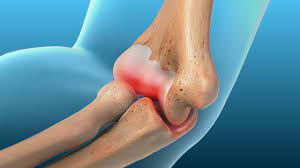

Schmerzen ellenbogen außen knochen. Eventuell können sie den Ellenbogen nicht mehr vollständig strecken und beugen. Dort sind sie mit kräftigen Knochenvorsprüngen den Epicondylen verbunden die am ellenbogenseitigen Ende des Oberarmknochens liegen. Betroffen sind die Sehne nansätze der Streckermuskeln des Unterarmes die ihren Ursprung oberhalb des Ellenbogengelenkes an der äußeren Seite des Oberarmknochens Humerus haben.

Ellenbogenschmerzen durch entzündliche Erkrankungen Zu den entzündlichen Erkrankungen die Schmerzen im Ellenbogen verursachen können gehören unter anderem. Der Tennisarm oder Tennisellenbogen Epicondylitis humeri radialis ist ein schmerzhafter Reizzustand des Ellenbogens. Diese Sehnenerkrankung entsteht durch eine längere Überbelastung der Muskelansätze am Oberarmknochen.

Man spricht dann von Osteochondrosis dissecans kurz. Die schmerzhafte Entzündung führt auch zur Knorpelerweichung und zum Knorpelabbau in den Gelenkflächen des Ellenbogengelenks. Wenn das Knochenfragment sich ins Gelenk verlagert besteht die Gefahr der akuten Einklemmung Knorpelschädigung und später einer Arthrose.

Arthritis im Ellenbogen führt zu stechenden Schmerzen und Entzündungen sowie Schwellung und Überwärmung im Gelenk. Elektrisierende Schmerzen am Ellenbogen. Werden die Muskeln angespannt entsteht Zug an der Stelle wo die Muskeln am Knochen ansetzen.

Das ist zunächst nicht weiter schlimm. Schmerzen im Außenbereich des Ellbogens Tennisarm Tennisellbogen oder Epicondylitis humeri lateralis Der laterale Epicondylus ist ein Knochenvorsprung außen am Ellbogen wo die Sehnen der Unterarmmuskeln ansetzen.